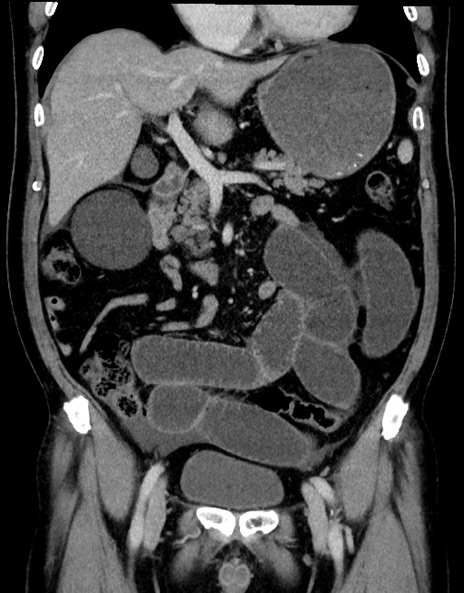

症例15(冠状断像)

【症例】70歳代男性

【主訴】腹痛

【現病歴】今朝から腹痛あり。全体的に痛い。特に左上の方。排ガスが今日はない。冷や汗が出る。

【既往歴】直腸癌術後

【身体所見】左側腹部〜上腹部に圧痛あり。腹膜刺激症状明らかなではない。軽度反跳痛。左下腹部に術後瘢痕あり。

【データ】WBC 7700、CRP 0.02